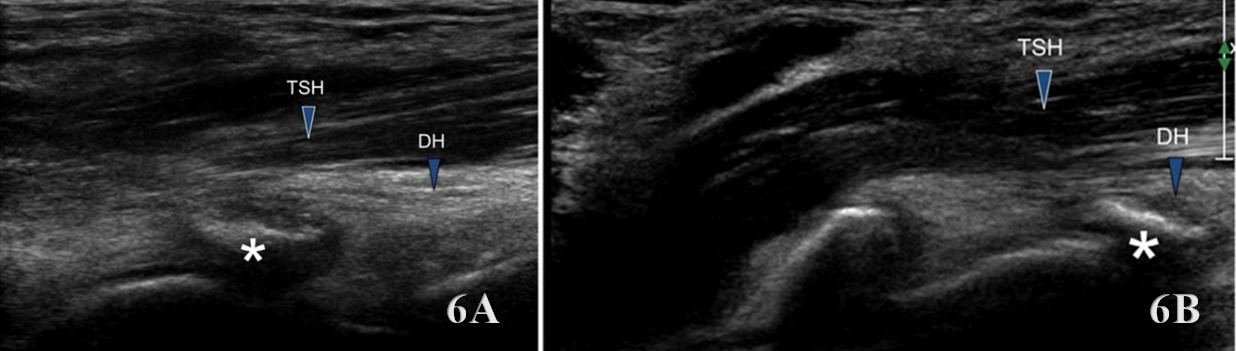

Examination Protocol

The brachialis is assessed using a linear high-frequency transducer (10–15 MHz), placed transversely over the distal anterior upper arm to identify the brachialis deep to the biceps brachii. In the short-axis (SAX) view, begin at the distal third of the humerus, visualizing the biceps superficially and the brachialis as a deeper, more hypoechoic structure adjacent to the humerus. Rotate the transducer 90° for a long-axis (LAX) view, tracing the muscle proximally toward the mid-humerus and distally to its insertion on the ulnar tuberosity.

Normal Sonographic Appearance

Normally the brachialis tendon is viewed in both LAX and SAX views. The brachialis tendon can be seen distally at the ulnar attachment. The hyperechoic outline of the ulna will be seen below the brachialis. The brachialis tendon will be more hyperechoic in appearance, while proximally from the ulna the brachialis muscle will be hypoechoic tissue. In the LAX view the muscle should be fibrillar. The soundhead may need to be toggled at the distal tendons insertion to avoid anisotropy. Dynamic visualization can be performed with resisted elbow flexion and forearm pronation and supination.20,21